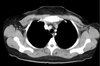

What are the three spaces in the chest?

Two pulmonary cavities and mediastinum